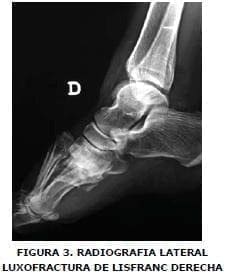

Se realizan radiografías y se hace diagnostico de fractura en articulación sacro ilíaca bilateral con subluxación del anillo pélvico superior de predominio izquierdo (Figura Nº 1), luxofractura de Lisfranc derecha (Figuras Nº 2 y 3), y luxofractura abierta tobillo izquierdo (Figura Nº4).

Se aplicó antibioticoterapia biconjugada y manejo de tejidos blandos. Quince días más tarde, se realizó reducción abierta con osteosíntesis definitiva con clavos de Kirschner en luxofractura de pie derecho tipo Lisfranc B2, con desplazamiento lateral. Encontrándose minutas en los metatarsianos (Figuras Nº 5 y Nº 6), en tobillo izquierdo se adelantó reducción abierta mas osteosíntesis con tornillos de esponjosa en superficie articular anterior de tibia distal y con clavo de Steinman se fijó articulación tibioastragalocalcanea, izquierda (Figura Nº 7). La paciente presento escaras sacras con evolución favorable y finalmente salió de alta hospitalaria a los 64 días de ocurrido el trauma.

Se aplicó antibioticoterapia biconjugada y manejo de tejidos blandos. Quince días más tarde, se realizó reducción abierta con osteosíntesis definitiva con clavos de Kirschner en luxofractura de pie derecho tipo Lisfranc B2, con desplazamiento lateral, encontrándose minutas en los metatarsianos (Figuras Nº 5 y Nº 6), en tobillo izquierdo se adelantó reducción abierta mas osteosíntesis con tornillos de esponjosa en superficie articular anterior de tibia distal y con clavo de Steinman se fijó articulación tibioastragalocalcanea, izquierda (Figura Nº 7).